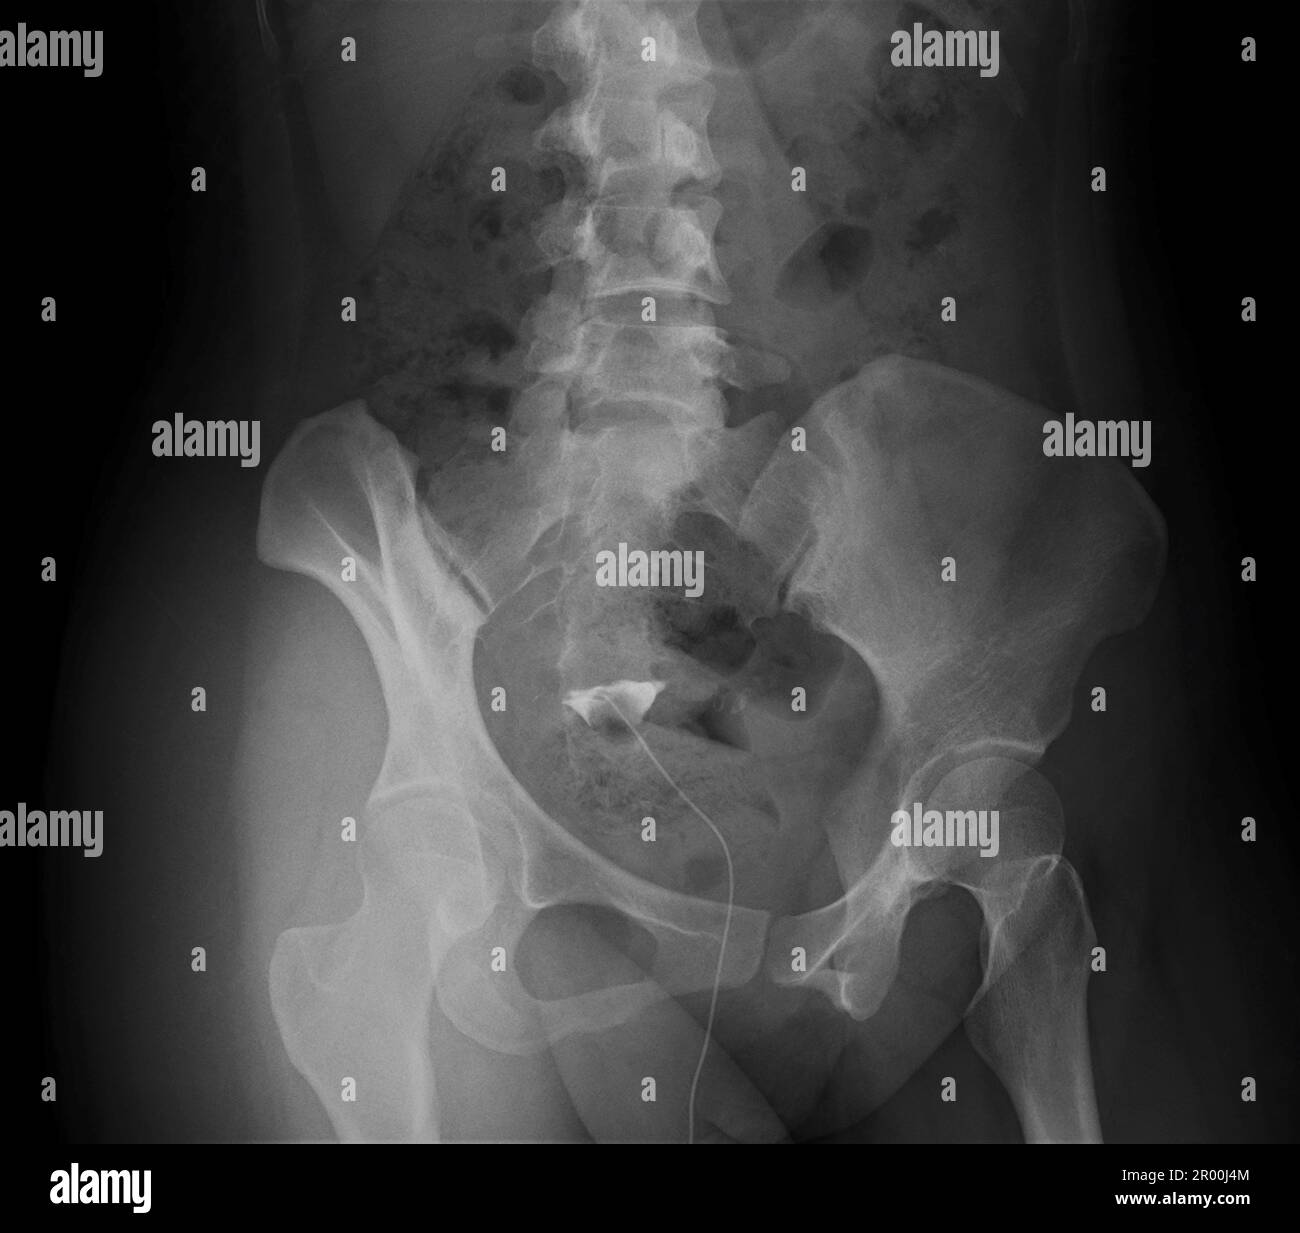

From www.alamy.com

Fallopian tube of a patient with infertility, Xray Stock Photo Alamy Dye X Ray Fallopian Tubes Once the area is numbed, your ob/gyn will use a small, thin tube or catheter to insert liquid dye into your cervix, which is used to see the outline of your uterus and fallopian. Hysterosalpingography (hsg), also known as uterosalpingography, [ 1 ] is a radiologic procedure to investigate the shape of the uterine cavity. It often is used to. Dye X Ray Fallopian Tubes.